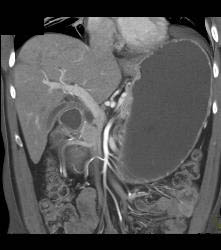

Antral Carcinoma- See Sequence